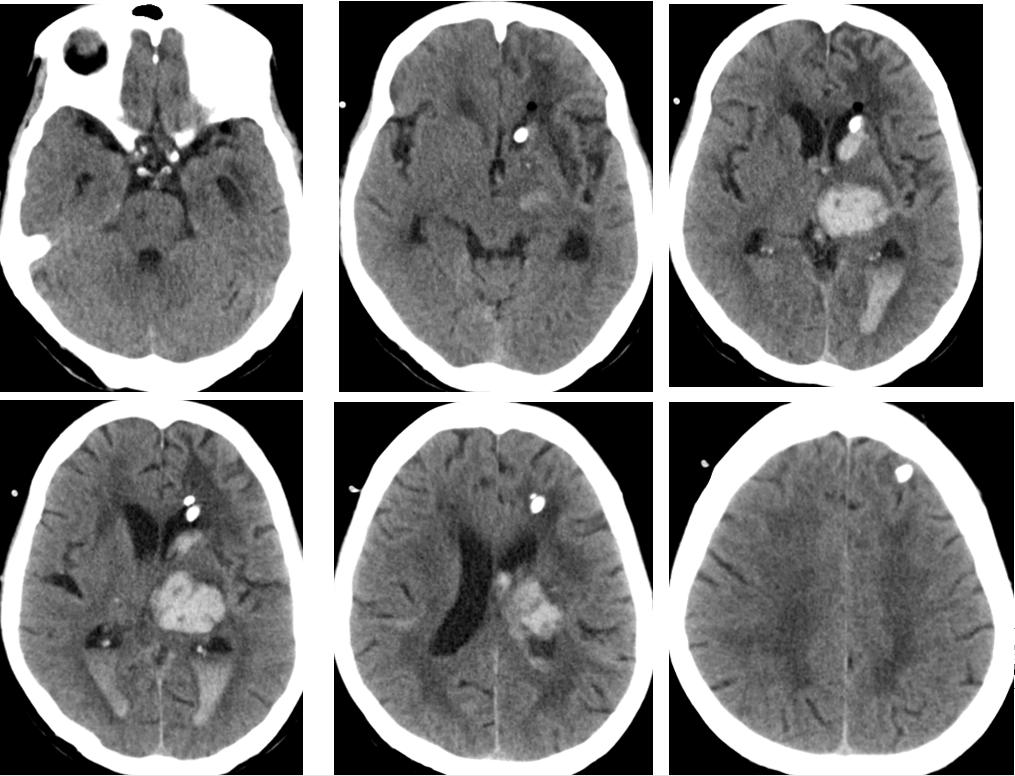

2014-11-24 CT

2014-11-20 CT

气颅、轻度脑积水,加强脱水,必要时用激素

2014-11-18 CT

2014-11-27 CT